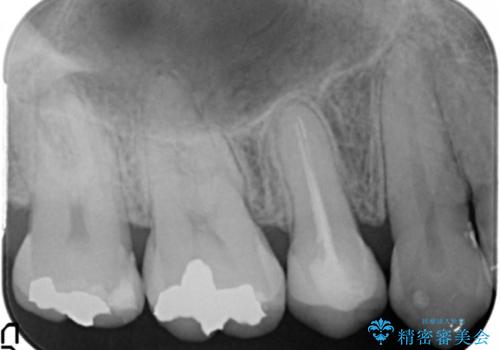

- 低予算で銀歯を白くしたいとご希望し来院された患者様です。

右上小臼歯(右上5)はオールセラミッククラウン(e-max press)、下顎臼歯(下顎両側67)はメタルボンドクラウンによりやりかえることにしました。

再根管治療はご希望されず、行っておりません。

右上小臼歯(右上5):オールセラミッククラウン エコノミー

下顎両側臼歯(下顎両側67):メタルボンドクラウン エコノミー